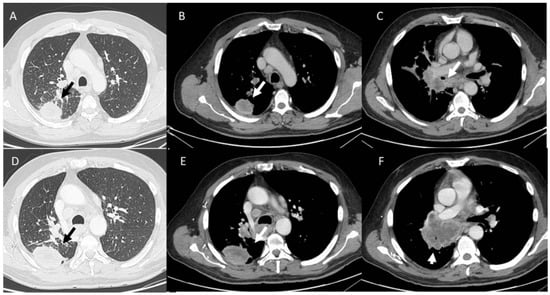

- Kalisz, K.R.; Ramaiya, N.H.; Laukamp, K.R.; Gupta, A. Immune Checkpoint Inhibitor Therapy-related Pneumonitis: Patterns and Management. Radiographics 2019, 39, 1923–1937. [Google Scholar] [CrossRef] [PubMed]

- Kwak, J.J.; Tirumani, S.H.; Van den Abbeele, A.D.; Koo, P.J.; Jacene, H.A. Cancer immunotherapy: Imaging assessment of novel treatment response patterns and immune-related adverse events. Radiographics 2015, 35, 424–437. [Google Scholar] [CrossRef]

- Wang, G.X.; Kurra, V.; Gainor, J.F.; Sullivan, R.J.; Flaherty, K.T.; Lee, S.I.; Fintelmann, F.J. Immune Checkpoint Inhibitor Cancer Therapy: Spectrum of Imaging Findings. Radiographics 2017, 37, 2132–2144. [Google Scholar] [CrossRef]